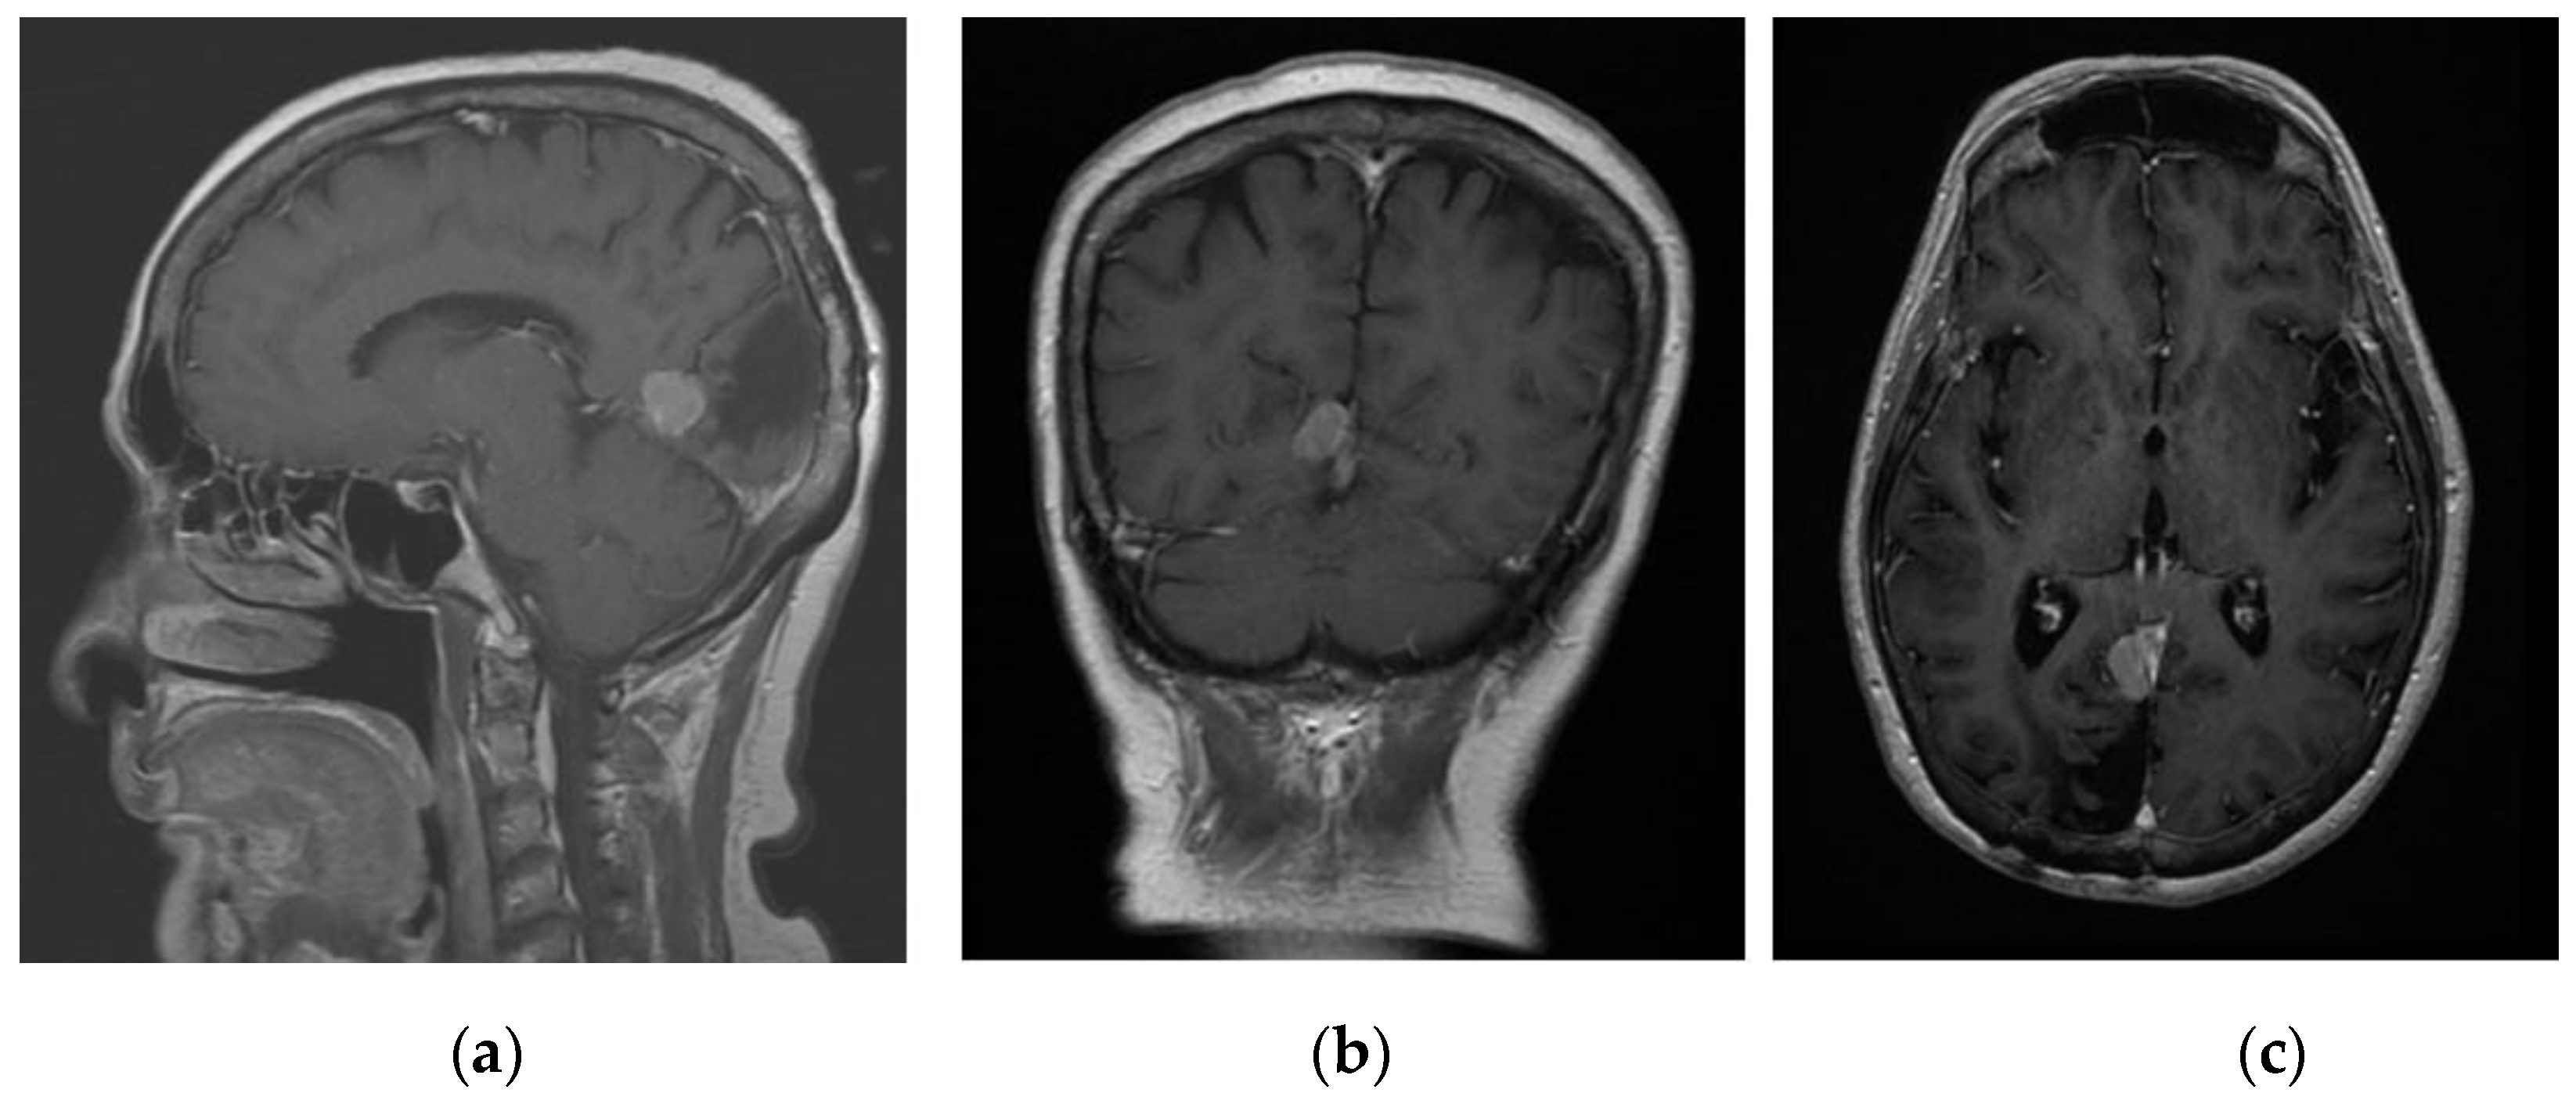

The first patient was a 72-year-old female with known history of right occipital parafalcine meningioma. The histology was consistent with that of atypical meningioma, WHO grade II. During follow up, she was noted to have recurrence of the lesion at the surgical bed, 1.5 cm in maximum diameter (Figure 1). The patient agreed for surgical resection of the lesion. As shown in Figure 1, patient’s tumour was deep seated, and an accurate neuronavigation was required to ensure that the tumour was resected. Standard neuronavigation MRI images were obtained for intra-operative planning. These images were then uploaded onto the HoloLens 2 system for rendering into a 3D image.

Figure 1. Contrasted T1 MRI: (a) sagittal, (b) coronal, and (c) axial planes showing recurrence of the lesion at the surgical bed, 1.5 cm in maximum diameter.